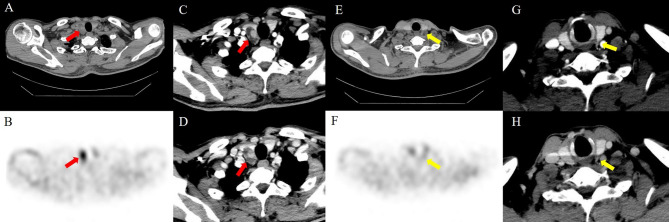

Objective: Accurate preoperative imaging localization is paramount to the success of targeted parathyroidectomy for primary hyperparathyroidism (PHPT). Four-dimensional (4D) CT is a promising method for preoperative localization of the parathyroid, but studies on the performance of 4D CT and technetium 99 m-sestamibi SPECT/CT for the diagnosis of diseases of the parathyroid are limited.

Materials and methods: To compare the diagnostic performance of sestamibi SPECT/CT and 4D-CT for preoperative localization in patients with PHPT in a single-institution from August 2017 to May 2024.

Results: Two hundred forty-two patients with PHPT (166 females; 52.5 years ± 13.4 [SD]) were evaluated. Among the 242 patients, 233 patients (96.3%) had single-gland disease, and 9 patients (3.7%) had multigland disease. Similar diagnostic performance was observed for sestamibi SPECT/CT and 4D-CT ([receiver operating characteristic ROC], 0.90 [95% CI: 0.87, 0.92] and 0.88 [95% CI: 0.85, 0.90], respectively; p = 0.11). Compared with 4D-CT, combined-modality sensitive reading and sestamibi SPECT/CT had the highest ROC, and, although there was no significant difference between the two (ROC, 0.91; 95% CI: 0.89, 0.93; p = 0.14), they significantly differed from 4D-CT (p = 0.0006). Sestamibi SPECT/CT showed an accuracy of 92% (95% CI: 90%, 94%), similar to 4D-CT (91%; 95% CI: 89%, 92%), combined-modality sensitive reading (91%; 95% CI: 89%, 93%) and combined-modality specificity reading (92%; 95% CI: 90%, 94%).

Conclusion: Sestamibi SPECT/CT has high accuracy in preoperative localization in patients with PHPT. Compared with sestamibi SPECT/CT alone, 4D-CT and combined-modality reading did not improve diagnostic performance.